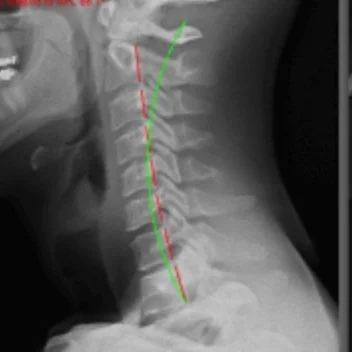

Navigating Cervical Retrolisthesis: A Comprehensive Guide to Understanding and Managing Neck Pain by Dr.Cho